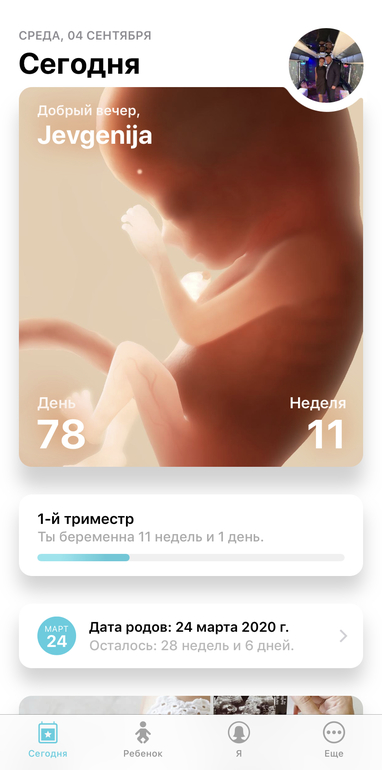

Ходили мы все же в платную клинику что бы убедится все же. Миомы подтвердились аж 2шт. Никогда их небыло, срок по узи 11 и 1. Показали малыша со всех сторон фото сделали сердечко дали послушать. Такая прелесть, я хоть чуток успокоилась. Он такой хороший малыш. Сказала ходите беременность спокойно, миомы вас не должны сейчас волновать.

Вот теперь правильный срок. Все будет хорошо! Доносим и родим здоровых малышей!!!

Всем спасибо, я говорю какое чудо эти современные аппараты узи. Не то что в наших больницах, напугала меня я сутки как истеричная беременная женщина. Как будто первый он у меня ребенок. Наверное чем старше тем страшнее. Спасибо беременяшечки всем спокойной беременности и хороших анализов.